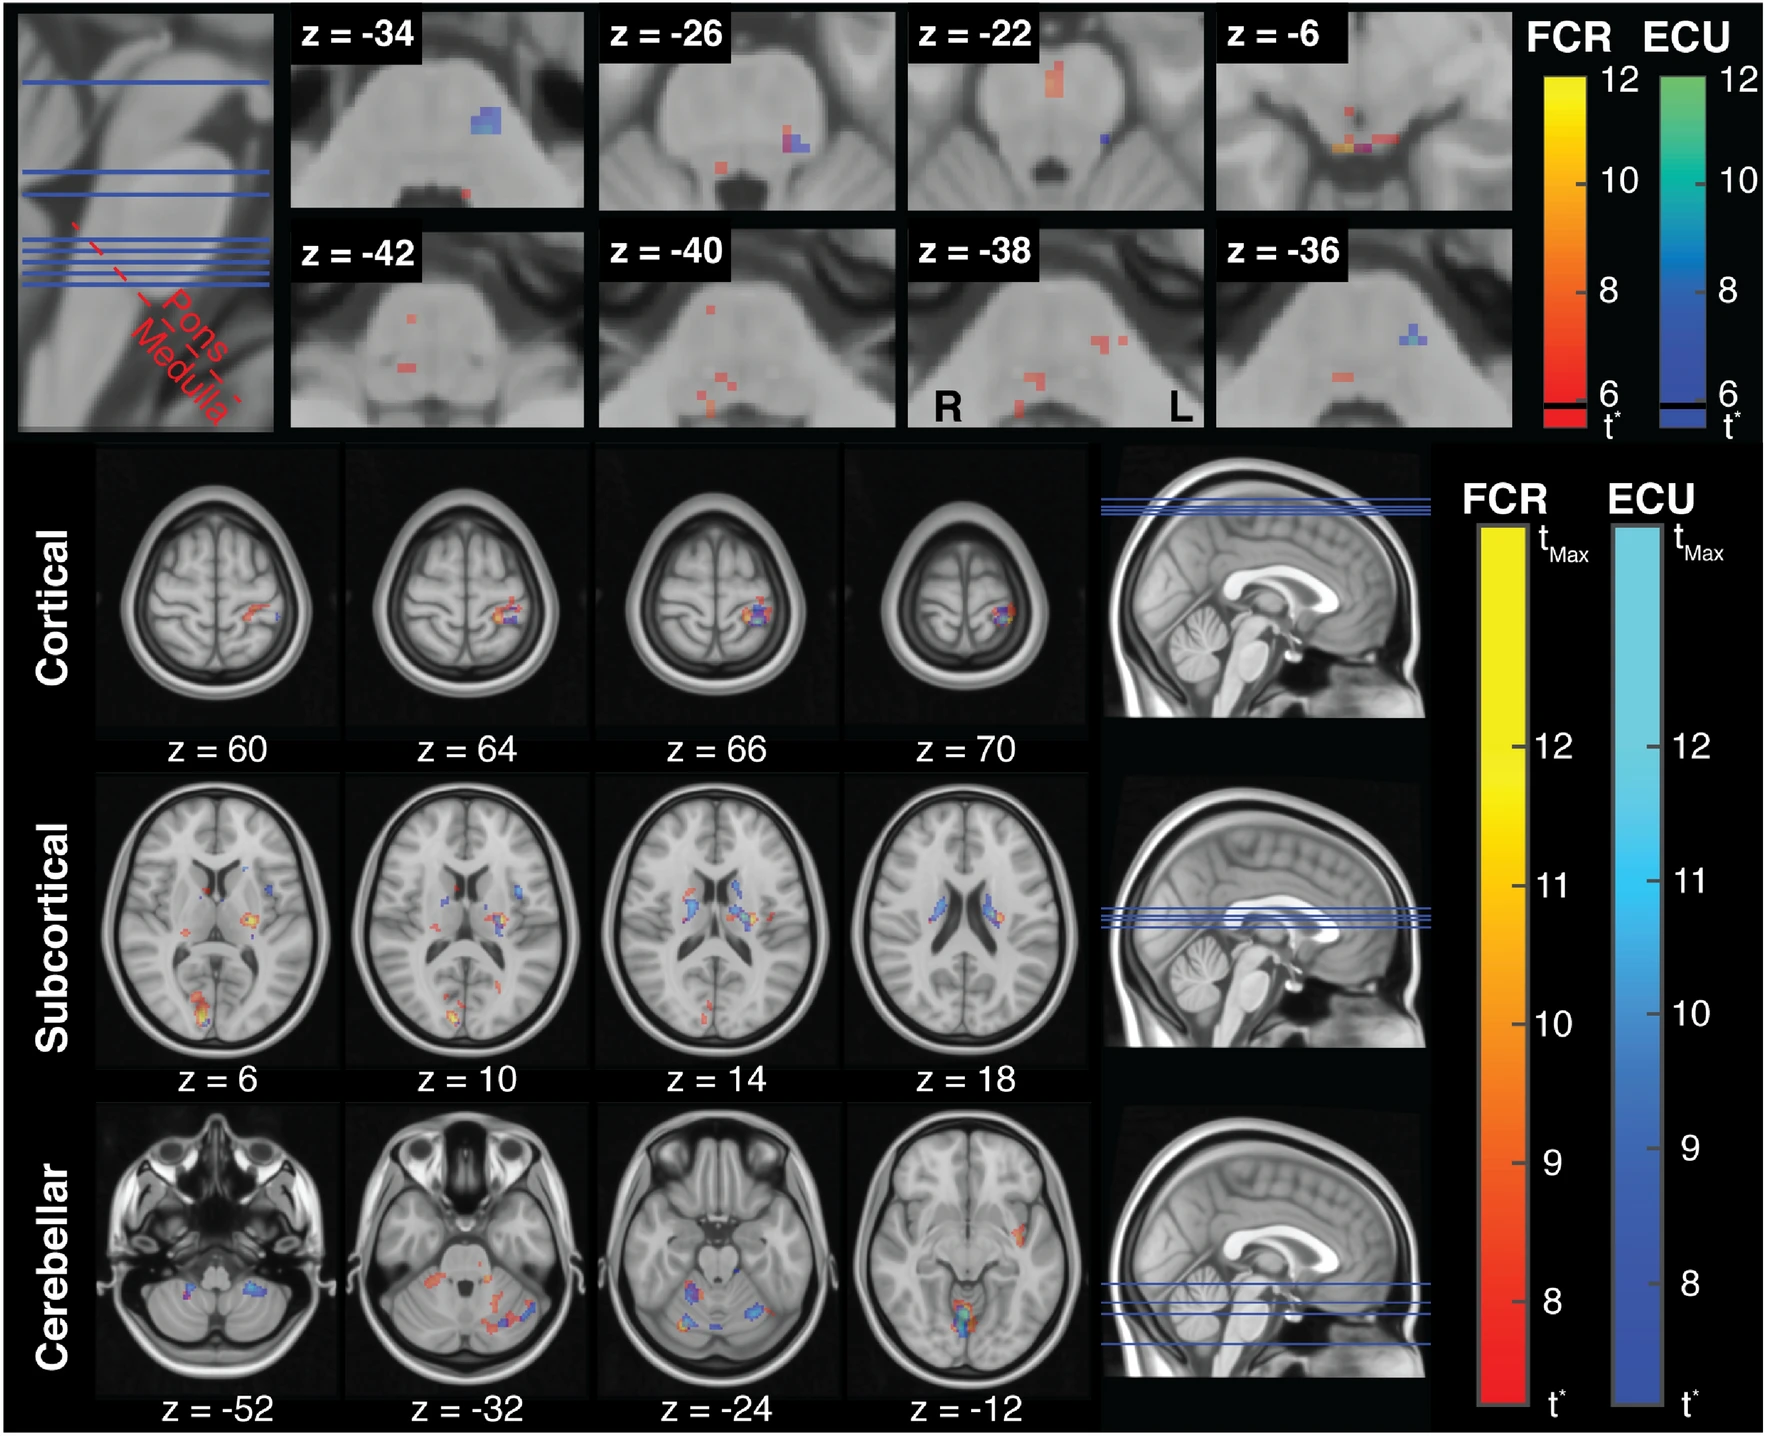

(above) Muscle specific organization of stretch-related activity in the brainstem. Stretch-related activity in the cortical, subcortical, and cerebellar brain regions associated with FCR and ECU activity.